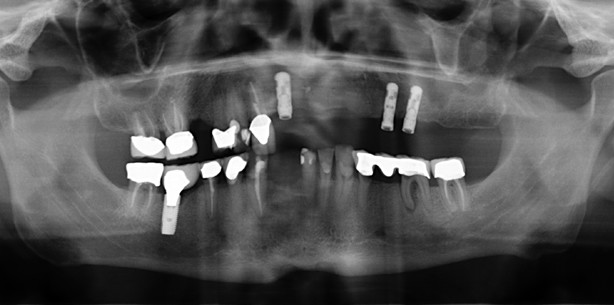

Im folgenden Fachbeitrag soll gezeigt werden, wie in der Praxis selten vorkommende Indikationen mit Implantaten gelöst werden können.

Im folgenden Fachbeitrag soll gezeigt werden, wie in der Praxis selten vorkommende Indikationen...